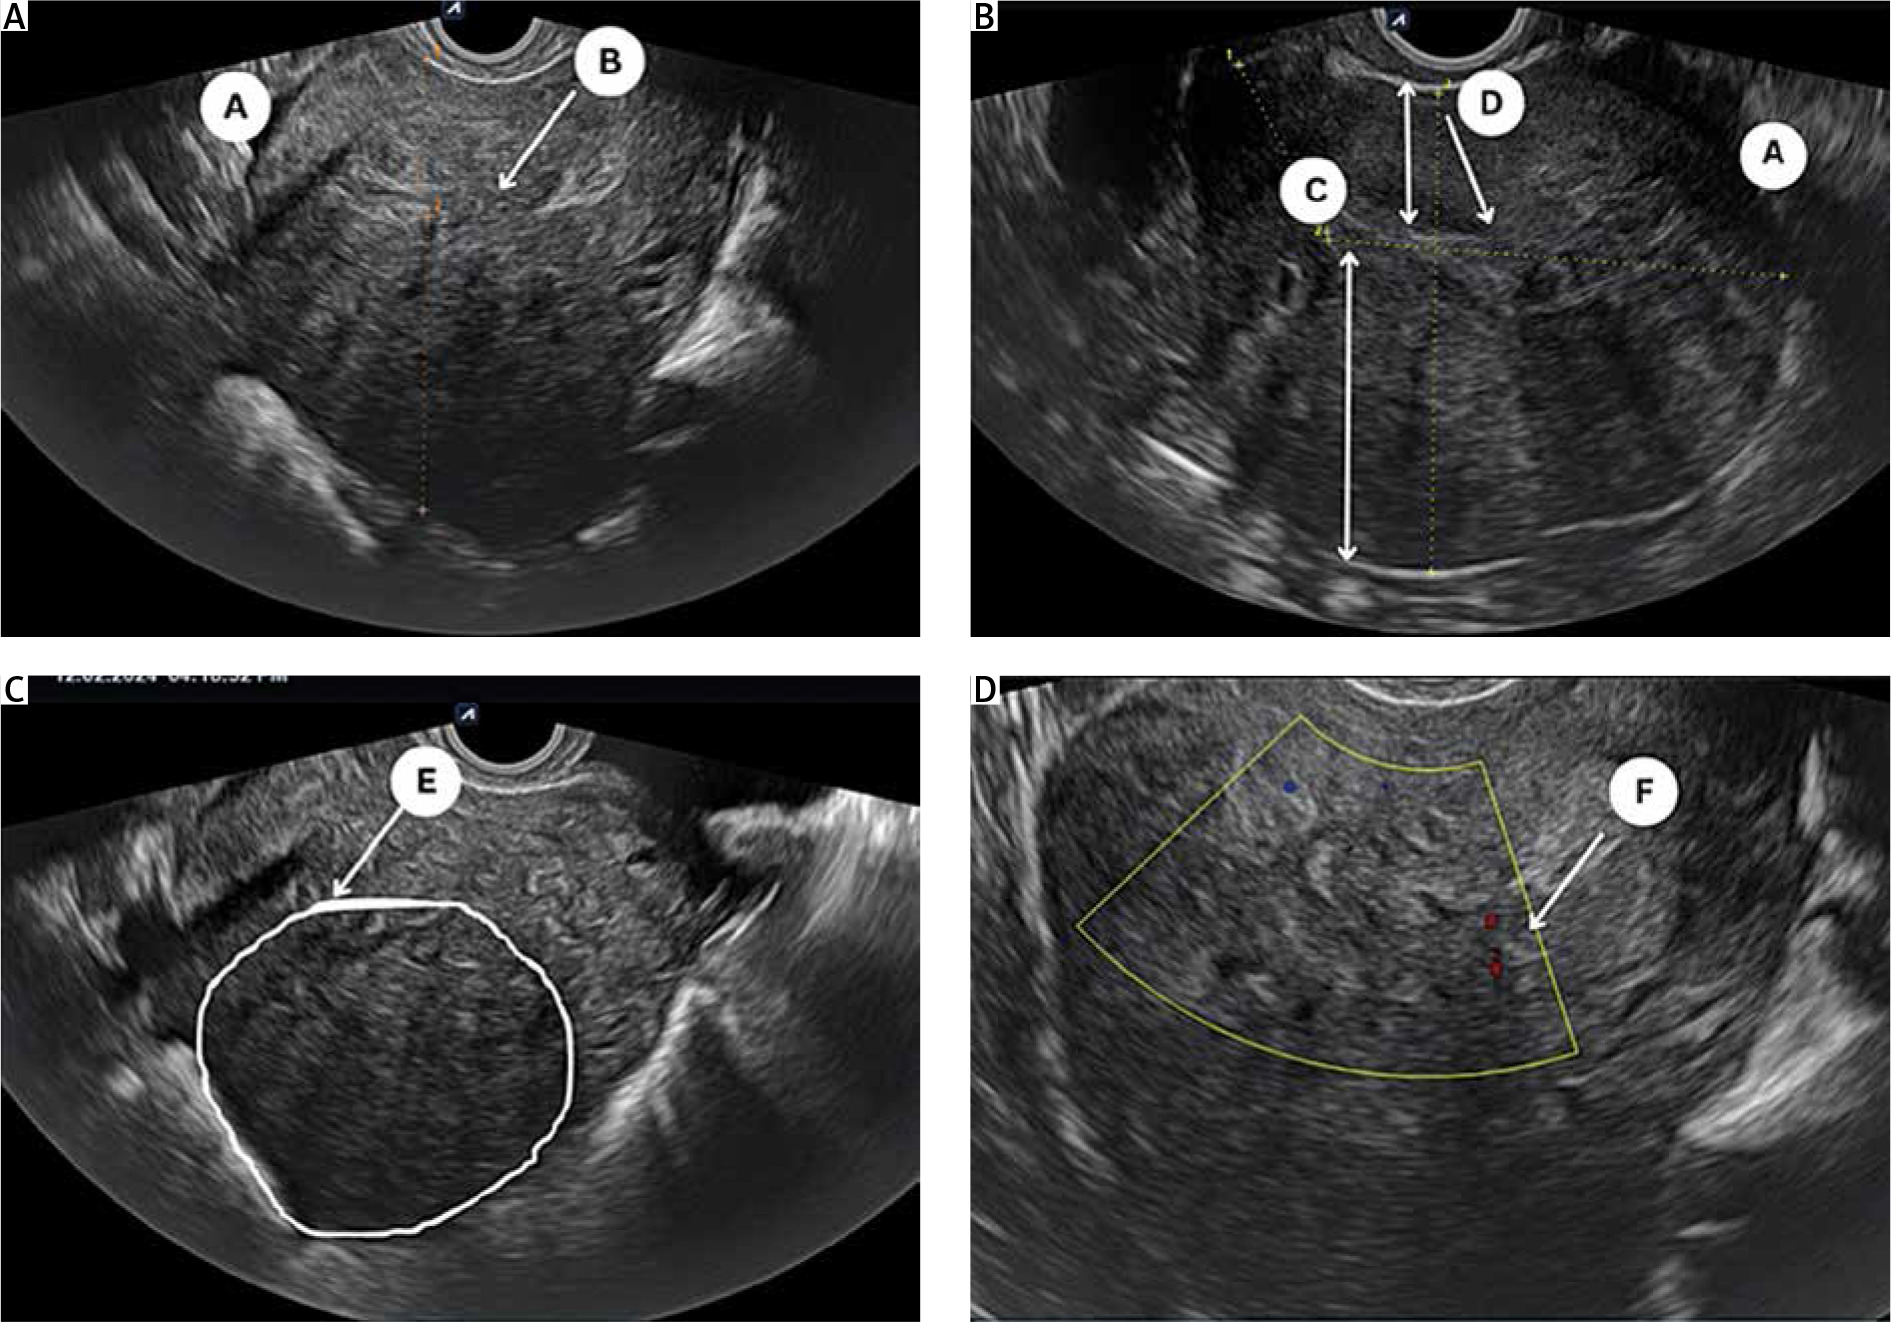

All eligible women underwent a detailed 2D-TVS with grey scale and power Doppler during the secretory phase of the menstrual cycle. All TVS were performed by 2 experienced sonographers (SJ and US) who were blinded to the patient’s clinical symptoms. A thorough evaluation of the pelvis was performed including the uterus (myometrium, endometrium, and junctional zone), bilateral adnexa, anterior and posterior compartment, rectum, bladder, rectosigmoid junction, presence of adhesion (sliding signs), site-specific tenderness, and translesional vascularity. Women with features of endometriosis (endometrioma or deep endometriotic nodule) or myoma were excluded from the study. A diagnosis of adenomyosis was established if one direct MUSA feature or one indirect MUSA feature with involvement of junctional zone was observed [9]. Direct features included were as follows: cysts in the myometrium; hyperechogenic islands; and echogenic subendometrial lines or buds (Fig. 1). Indirect features included those secondary to the presence of endometrial tissue in the myometrium, such as globular uterus, asymmetrical myometrial thickening, fan-shaped shadowing, translesional vascularity, irregular junctional zone, and interrupted junctional zone (Fig. 2). Adenomyosis was defined as diffuse if < 25% of the lesion was surrounded by normal myometrium, provided that > 25% of the entire myometrium was involved, and focal if > 25% of the lesion surrounded by normal myometrium [7].